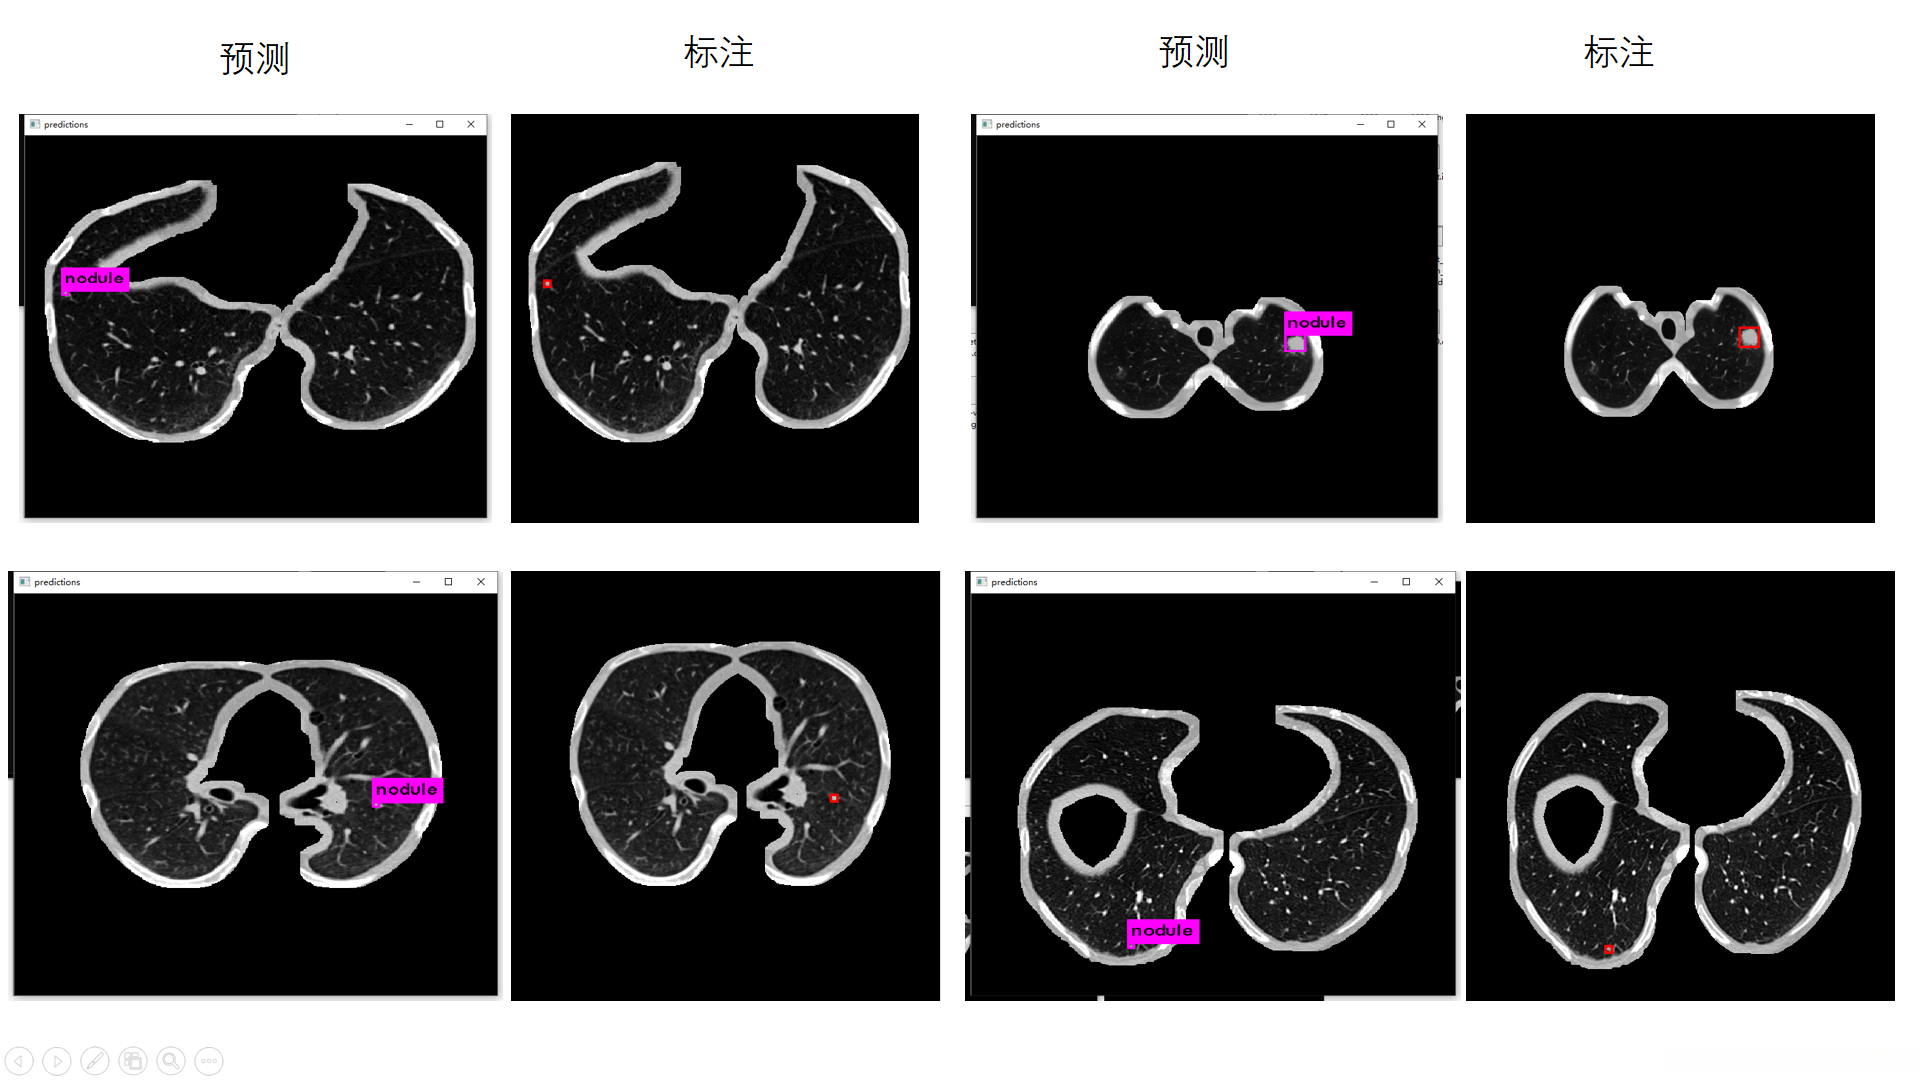

3. 检测效果预览

3.2 训练结果显示

训练了大概3天,迭代了48000次,loss值约0.03(GTX1080)。

原图:

预测:

标注图(根据标注生成):

在应用yolov3算法进行肺结节检测时,发现其在实际应用中仍存在一定局限性。具体表现为:1)迭代训练不足导致模型尚未达到充分收敛的状态;2)有必要对训练数据集进行聚类分析以优化参数设置,并调整anchor框大小与比例参数设置以进一步提升检测精度。

更新:2019.9.14

使用分割后的数据进行训练

经过大约四天的训练后确实比之前有了显著提升

下图左边是预测,右边是根据标注生成的ground truth。